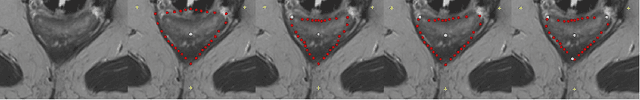

In this contribution, a semi-automatic segmentation algorithm for (medical) image analysis is presented. More precise, the approach belongs to the category of interactive contouring algorithms, which provide real-time feedback of the segmentation result. However, even with interactive real-time contouring approaches there are always cases where the user cannot find a satisfying segmentation, e.g. due to homogeneous appearances between the object and the background, or noise inside the object. For these difficult cases the algorithm still needs additional user support. However, this additional user support should be intuitive and rapid integrated into the segmentation process, without breaking the interactive real-time segmentation feedback. I propose a solution where the user can support the algorithm by an easy and fast placement of one or more seed points to guide the algorithm to a satisfying segmentation result also in difficult cases. These additional seed(s) restrict(s) the calculation of the segmentation for the algorithm, but at the same time, still enable to continue with the interactive real-time feedback segmentation. For a practical and genuine application in translational science, the approach has been tested on medical data from the clinical routine in 2D and 3D.